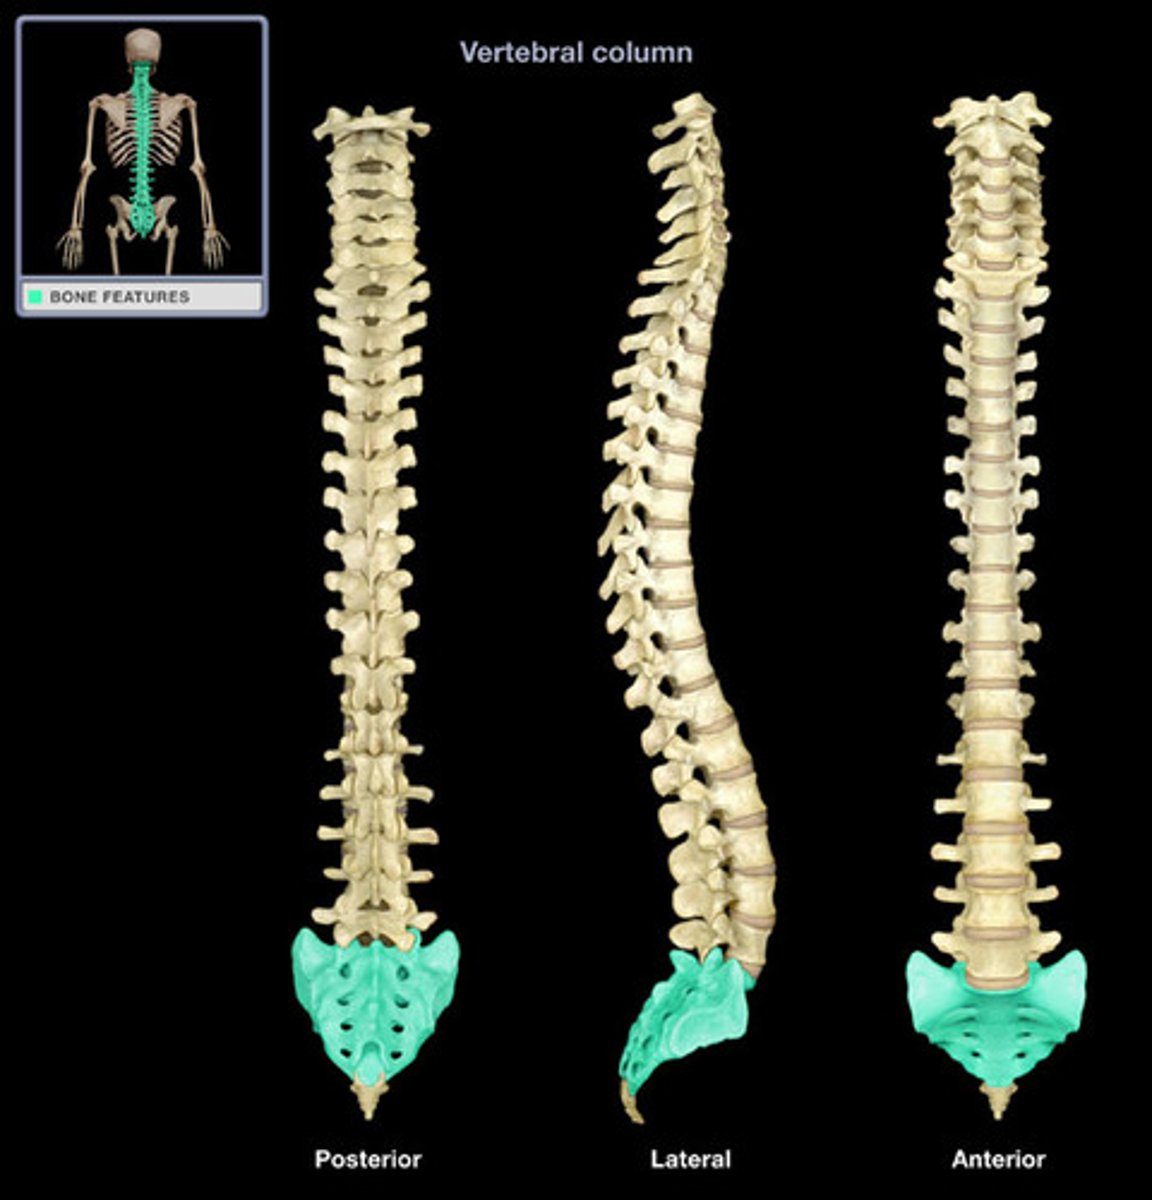

Spine (C/T/L), Sacrum & Coccyx

What are the sections of the vertebral column?

cervical, thoracic, lumbar, sacrum, coccyx

True/False: in males, the sacral bone is usually longer, narrower, and more evenly curved than in females

true

What is the superior portion of the sacrum called?

base

What is the inferior portion of the sacrum called?

apex

What is the sacral promontory?

prominent ridge on superior anterior margin of base

What is the sacral canal?

continuation of vertebral canal

The pelvic sacral foramen provide passage for what?

nerves and blood vessels

What is the auricular surface?

where the ilium articulates with the sacrum

How is the median sacral crest formed?

by fused spinous processes of the sacral vertebrae

The coccyx is commonly referred to as the ________

tailbone

True/False: the coccyx diminishes in size from base (superior) to apex (inferior)

true

Does the coccyx tend to curve more anteriorly in males or females?

males